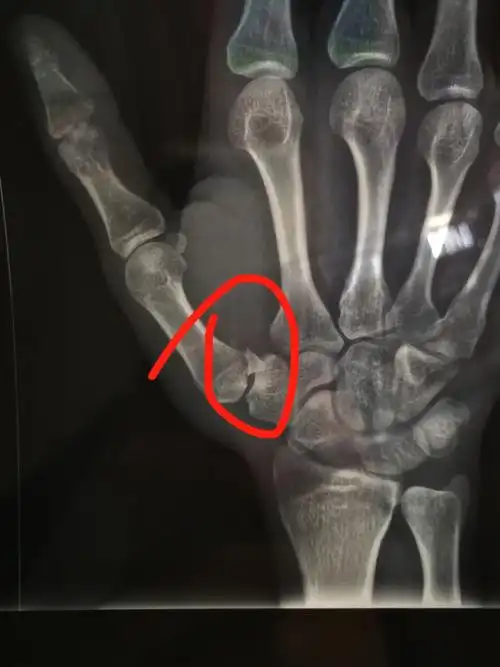

第1掌骨基底骨折1例 请各位老师指点

本耐氏bennett骨折即第一掌骨基底部骨折伴脱位

第一掌骨基底部骨折

病例讨论第一掌骨基底部骨折闭复内固定一例